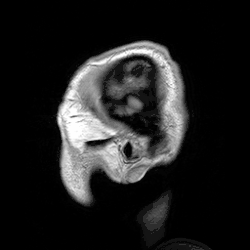

Neuroimagem

Diversos métodos de mapeamento cerebral são utilizados para compreender o cérebro humano.[40]